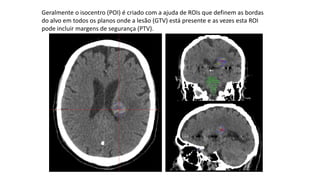

Geralmente o isocentro (POI) é criado com a ajuda de ROIs que definem as bordas

do alvo em todos os planos onde a lesão (GTV) está presente e as vezes esta ROI

pode incluir margens de segurança (PTV).